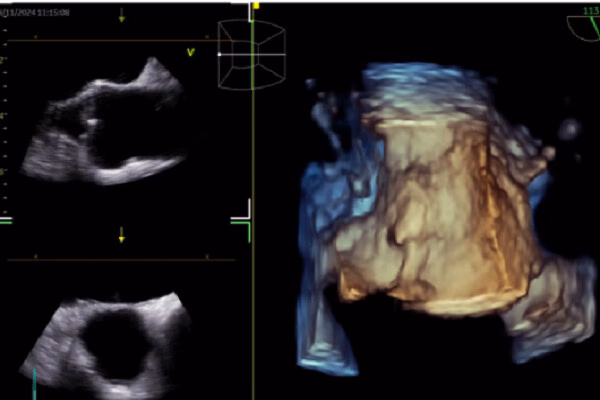

Siêu âm tim cũng là một lĩnh vực được ứng dụng AI rộng rãi. AI giúp nhận diện cấu trúc cơ tim, hỗ trợ đo đạc tự động và tạo báo cáo chẩn đoán. Việc sử dụng AI trong siêu âm tim không chỉ giúp tăng độ chính xác mà còn giảm thiểu thời gian thực hiện.